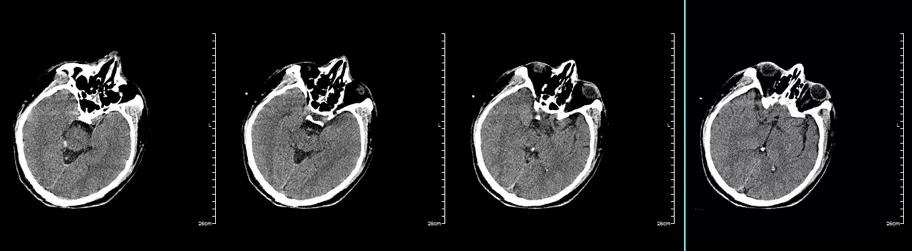

入院时头颅CT(图2):少量蛛网膜下腔出血。

图2. 入院时头颅CT